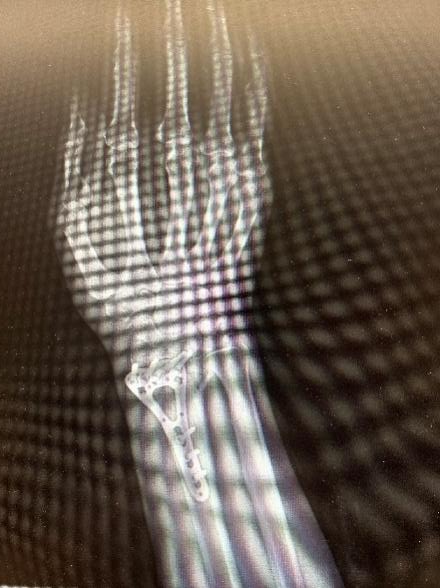

经急诊检查后明确左髌骨粉碎性骨折

图片

12:00入院

排除手术禁忌

15:00手术

创伤中心医师赵一峰

张翔主治医师为患者

急诊做了

左髌骨骨折切开复位克氏针张力带内固定术

术后予以中药活血化瘀、强筋健骨调理